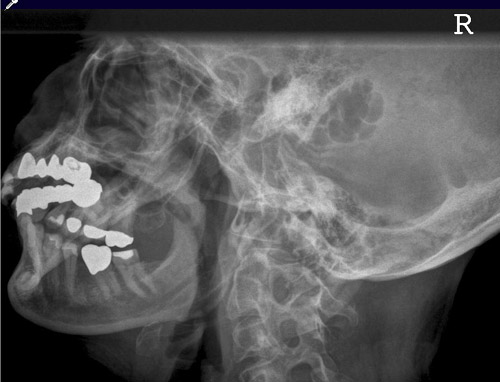

Unterkiefer

74_2.jpg

Fehler

Das Kieferköpfchen, resp. der Kieferhals sind nicht abgebildet. Es legt sich die obere HWS darüber.

Abhilfe

Der Kopf war zwar richtig seitlich zum Film geneigt, aber, für eine Darstellung des horizontalen Unterkiefers bis zum Eckzahngebiet, mit dem Kinn zu wenig dem Film genähert.